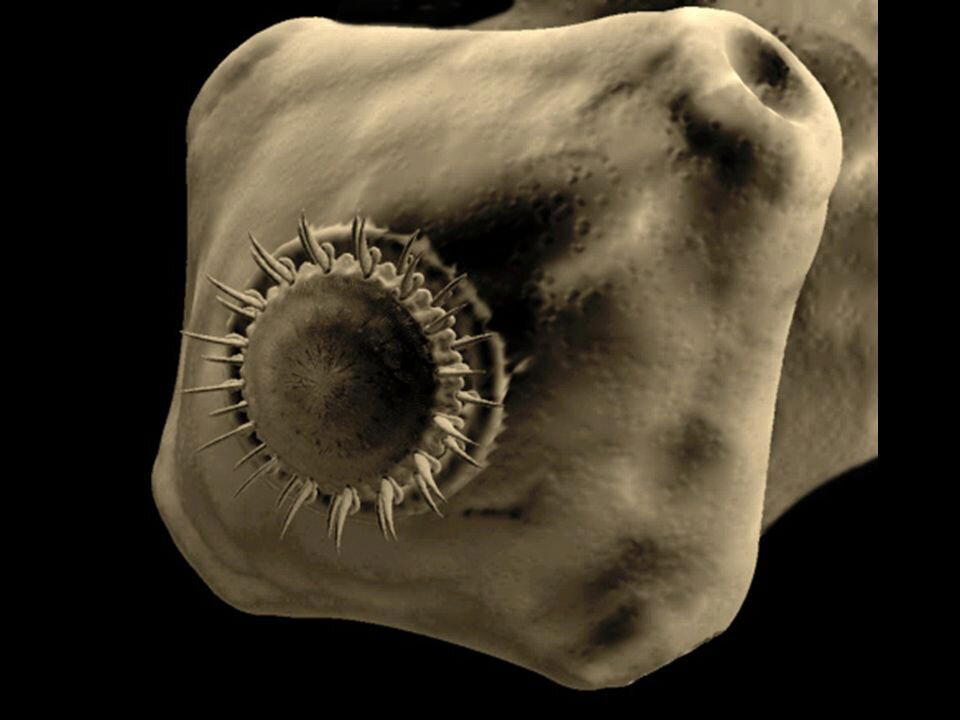

Потом мы посоветовались с моей помощницей как быть. Ведь человек нуждался в помощи. И чем скорее тем лучше. Мы с адреса остеохондроз возим только при тазовых нарушениях (это когда человек уже не может контролировать мочеиспускание и дефикацию, то есть ходит под себя). И с таким направлением только в нашу больницу могли отвезти. В общем мы решили слукавить. Написали диагноз: "Компрессионный перелом позвоночника". Решили так же рассказать немного другую историю - разгружал фуру и почувствовал боль в спине. Остальное совпадало с тем, что было на самом деле. Мужчину отвезли в Екатеринбург согласно маршрутизации в двадцать третью больницу к травматологам, чтобы сделали КТ. Кроме того, в этой больнице есть хорошее отделение неврологии. И операции на позвоночнике там делают с малым доступом. В общем - всё для пациента.